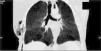

A right chest tube was placed after the diagnosis of a pneumothorax on the chest X-ray and permitted to obtain a clinical improvement. Due to the persistence of an atelectasis of the left upper lobe, a chest CT scan was performed and allowed to identify a round image of 5mm in relation with a foreign body, 3.8mm distal to the carina, which occupied the left main bronchus (Fig. 1). Given the stable clinical situation, we decided to perform a rigid bronchoscopy to extract this foreign body under general anesthesia, using HFJV (FiO2=1; pressure of 2atm; f=150cycles/min, and I-time of 50%), once the patient had accomplished the fasting time of 6h.